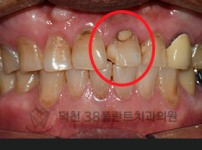

치료전후